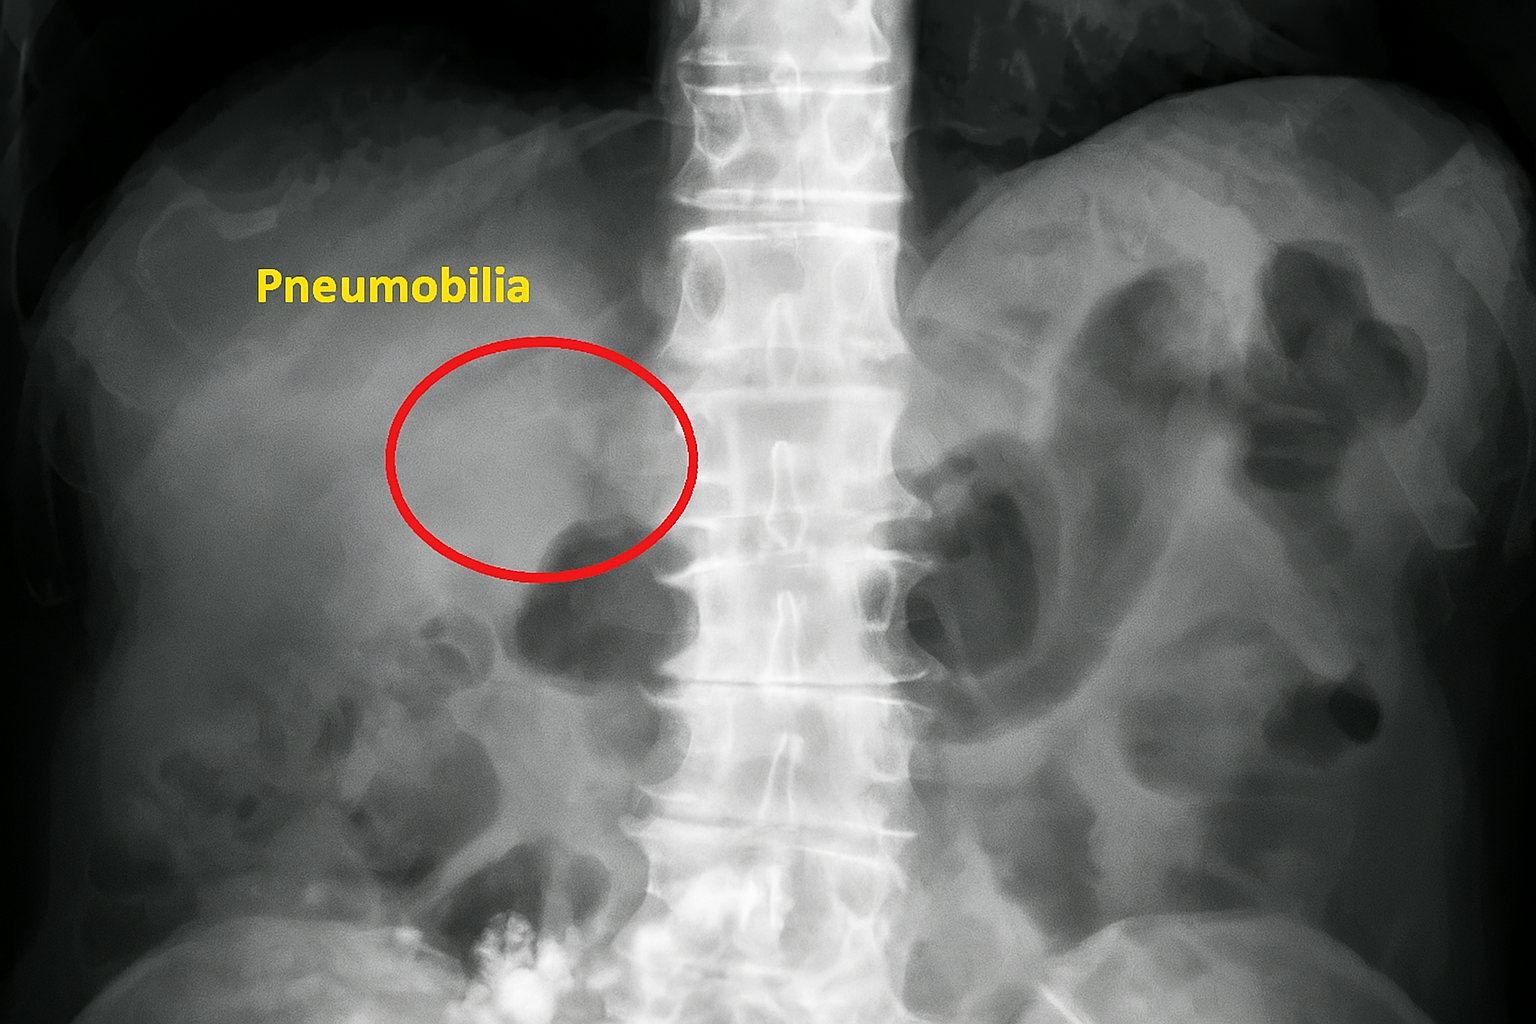

Aerobilia tipik olarak, yüksek oranda yansıtıcı alanlar olarak göründüğü ultrason veya karaciğer veya safra ağacı içinde dallanma düzeninde hava kabarcıkları gösterebilen bilgisayarlı tomografi (BT) gibi görüntüleme teknikleri kullanılarak teşhis edilir. Bu hava paternleri, görüntülemede benzer şekilde ortaya çıkabilen portal venöz gazdan ayırt edilmelidir (Sherman & Tran, 2006; Pai & Bude, 2002).

- 1970’lerde ve 1980’lerde görüntüleme teknolojilerinde, özellikle ultrason ve bilgisayarlı tomografi (BT) alanlarındaki gelişmelerle birlikte aerobilinin tespiti ve teşhisi daha kesin hale gelmiştir. Lewandowski ve arkadaşları (1984)* gibi çalışmalar, radyografik görüntülemede pnömobiliyi portal venöz gazdan ayırt etmeye yardımcı olan “kılıç işareti” gibi spesifik radyografik işaretleri tanıtmıştır.